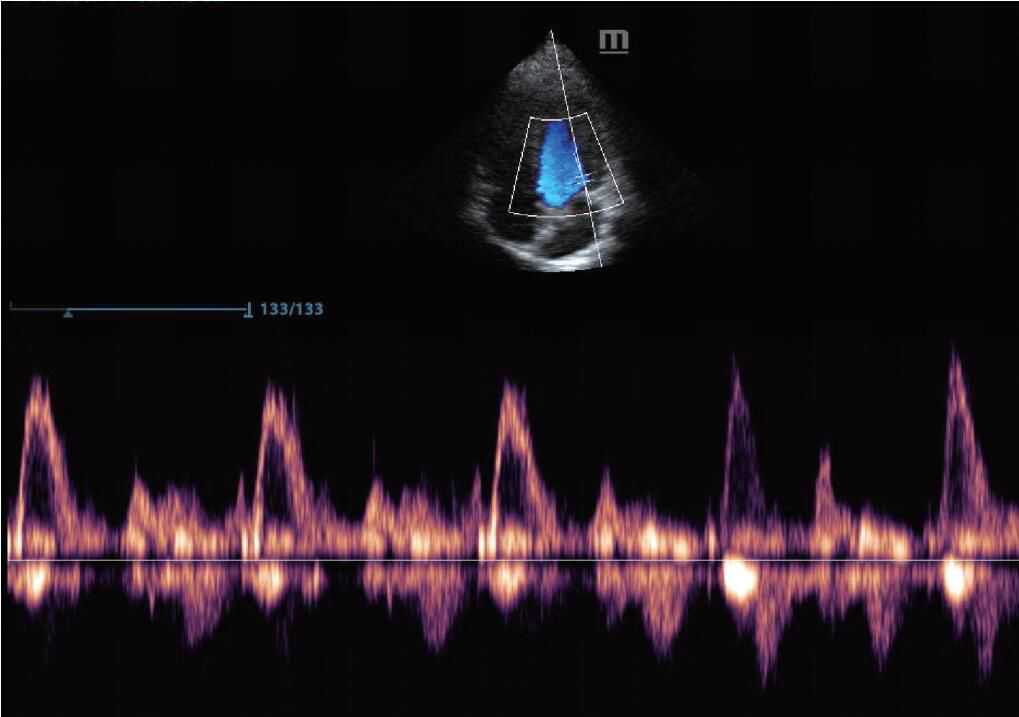

4.D模式是利用“多普勒效应”,在B模式图像上加以颜色实时显示血流(彩色多普勒,图3),或将目标血流信息以频谱形式表现(频谱多普勒)的模式。

图3D模式